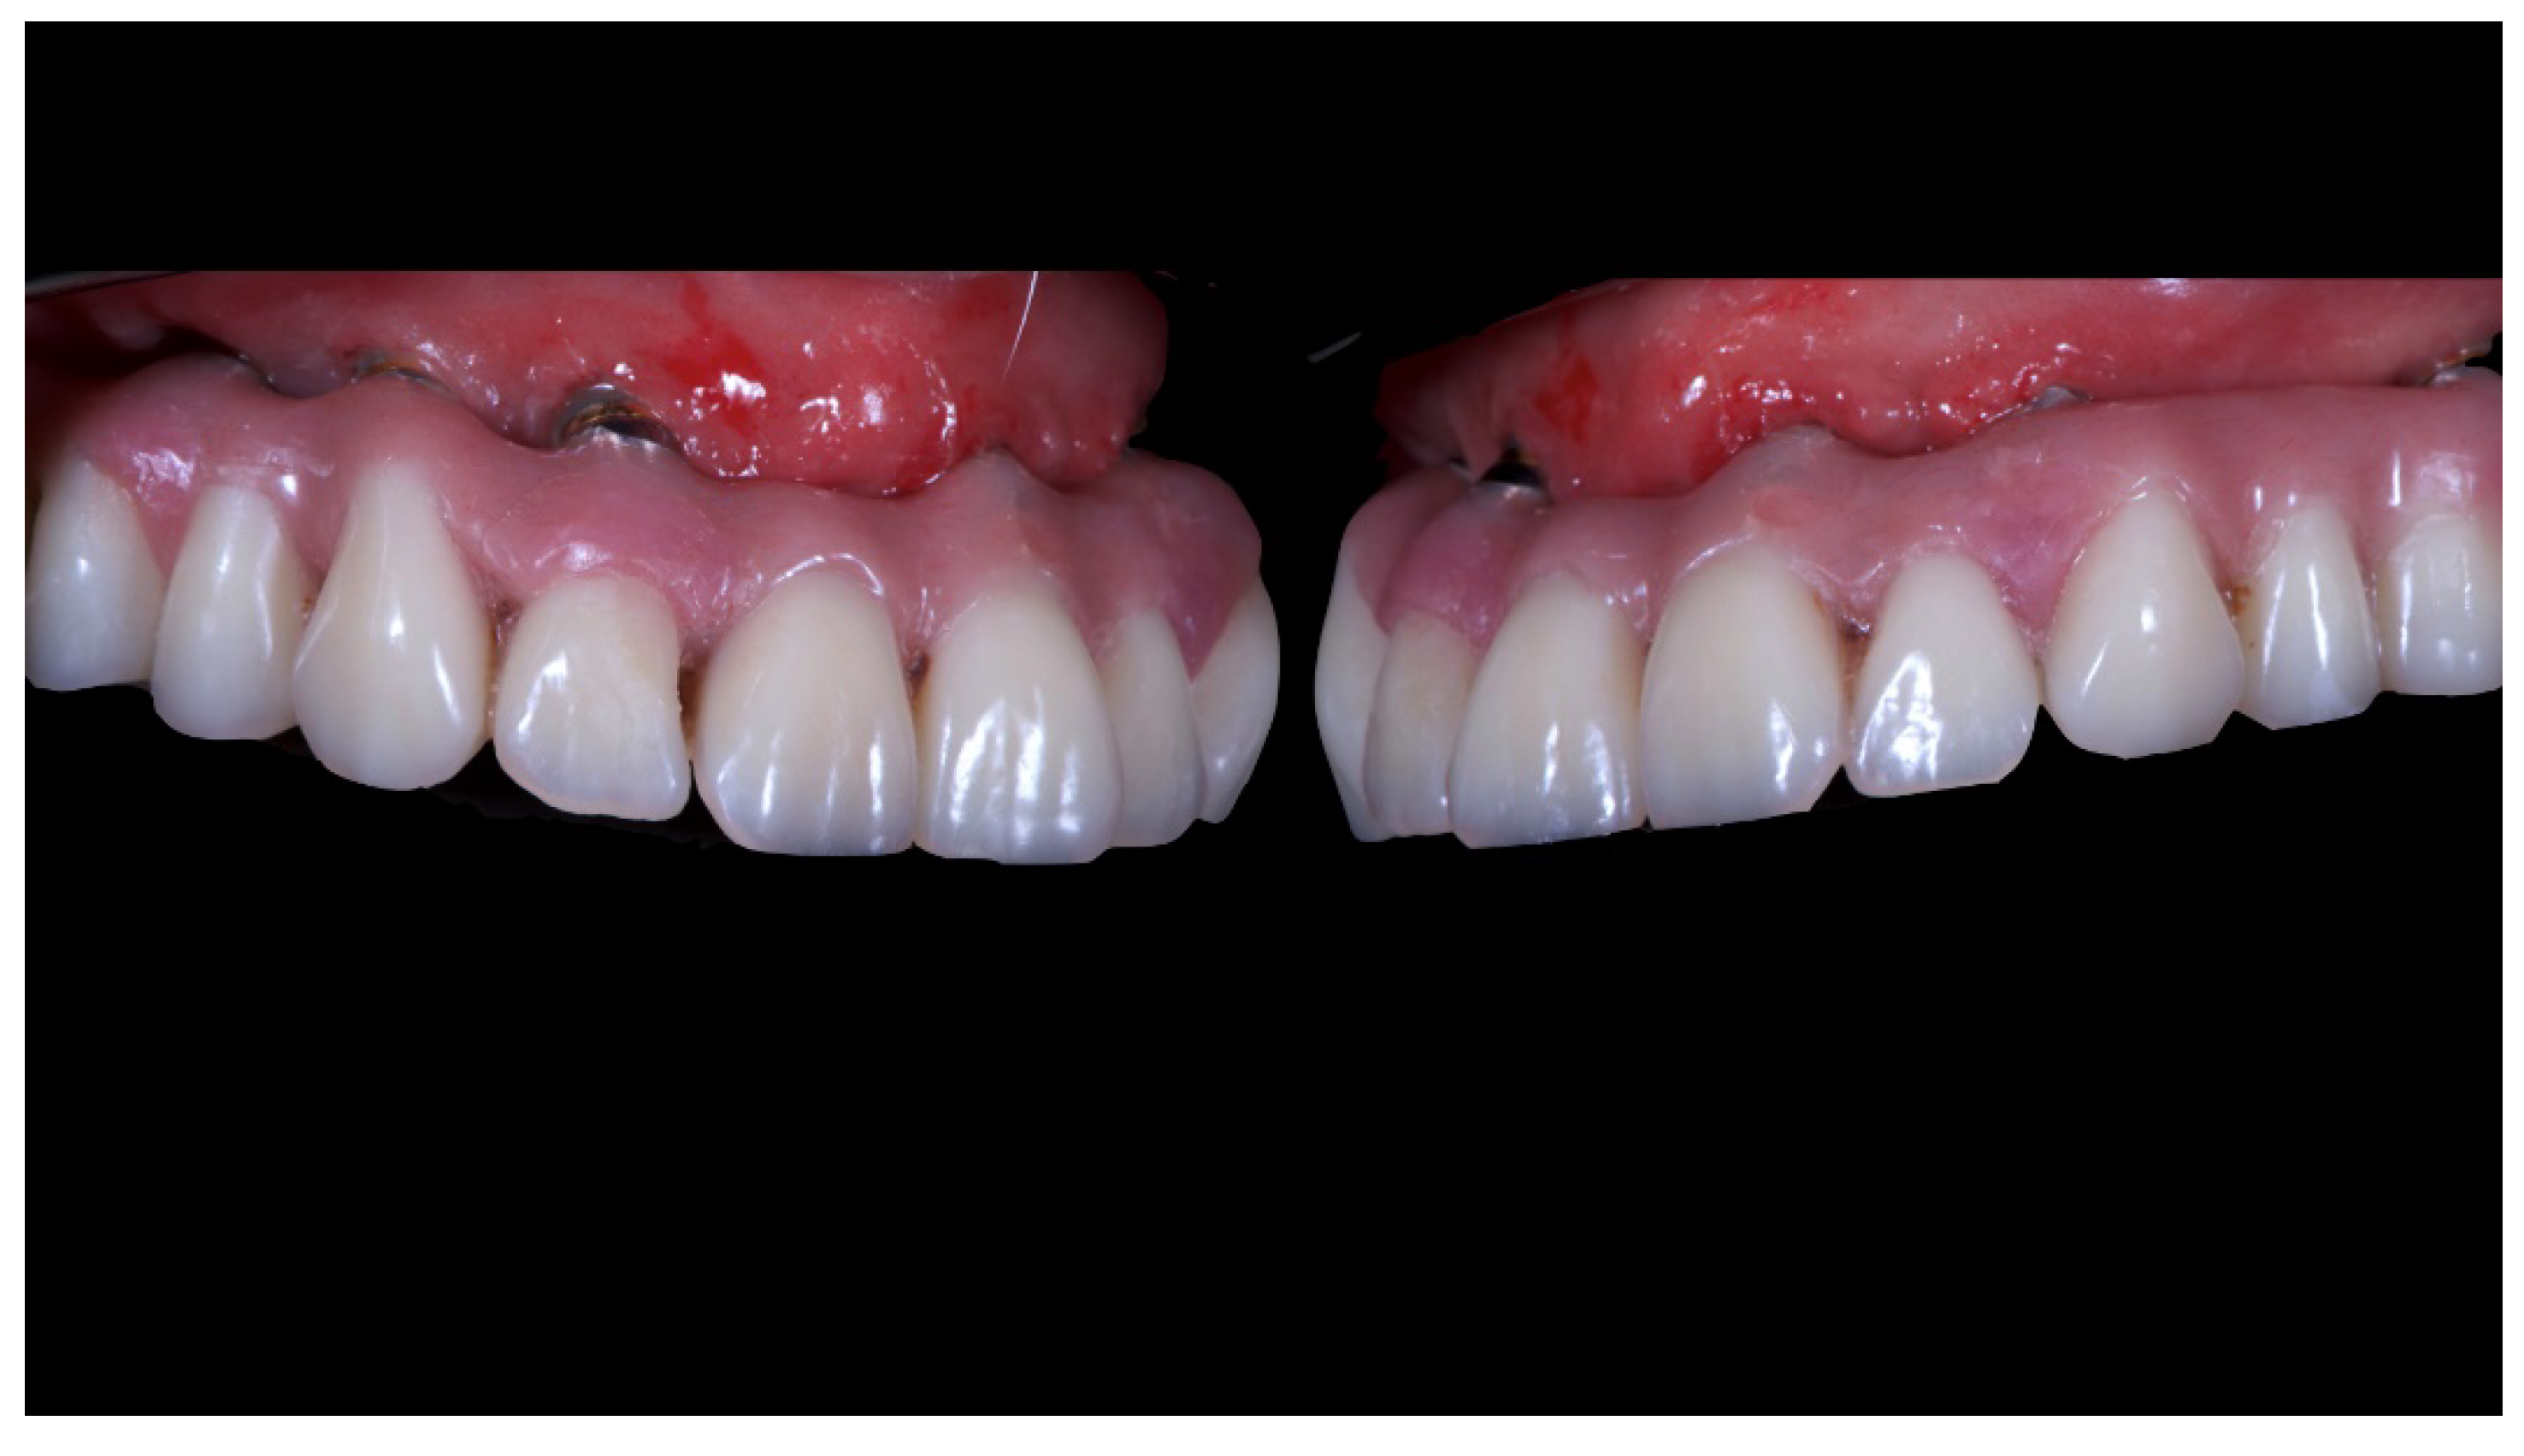

Figure 5.

Intraoral picture of the implant positions and the multi-unit abutment screwed on.